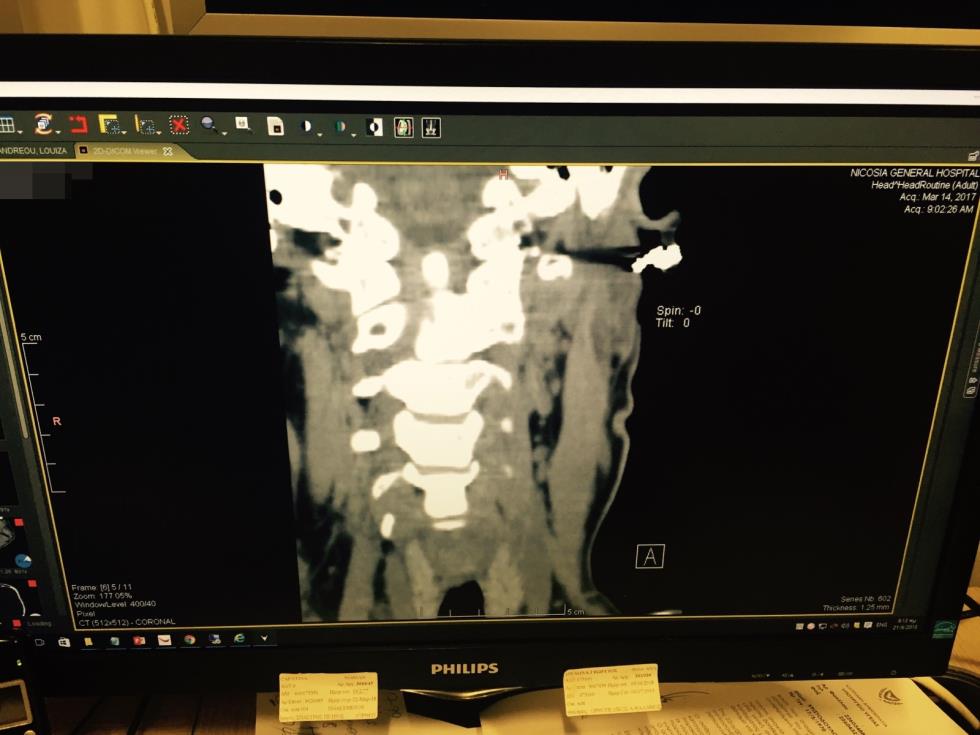

Στην τρίτη σελίδα, στην κατηγορία ΕΡΓΑΣΤΗΡΙΑΚΕΣ ΕΞΕΤΑΣΕΙΣ, προκύπτει ότι η ασθενής υποβλήθηκε σε Ακτινογραφίες και Αξονική τομογραφία, δίπλα από την οποία γράφει «head».

Από εκεί και πέρα, εντός του report επισυνάπτεται η εξέταση του θύματος από το ακτινολογικό τμήμα του νοσοκομείου, όπου καταγράφονται τα εξής:

- ΘΜΣΣ (Θωρακική Μοίρα Σπονδυλικής Στήλης)

- ΟΜΣΣ (Οσφυϊκή Μοίρα Σπονδυλικής Στήλης)

- ΑΜΣΣ (Αυχενική Μοίρα Σπονδυλικής Στήλης)

Πέραν του report, η πηγή επισυνάπτει ακτινογραφίες που λήφθηκαν, στις οποίες καταγράφεται το όνομα της ασθενούς, ημερομηνία και ώρα, στην βάση των οποίων φαίνεται καταγράφεται η πιο πάνω διάγνωση.

Επίσης, παραπέμπει και στις καταχωρήσεις που έγιναν στο Τμήμα Πρώτων Βοηθειών του Γενικού Νοσοκομείου Λευκωσίας, όπου καταγράφεται η επίσκεψη και διάφορα άλλα στοιχεία.